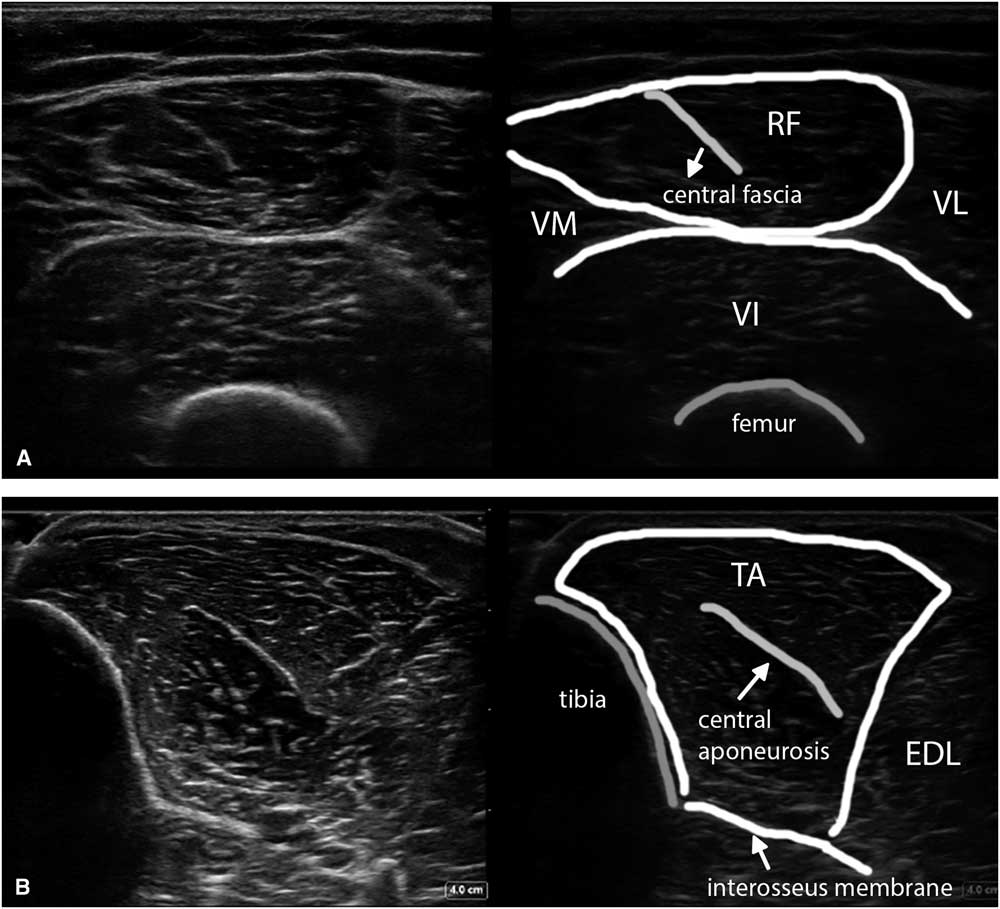

For identification of a specific muscle in its anatomical context and assessing echogenicity, transverse images work best, whereas assessment of fiber direction and disruption (as in muscle tears) and pennation angles require longitudinal images (Figure 1B). Just as with identifying nerves, here too it is advisable to use standard landmarks that will always show the way to the specific muscle of interest. For example, in the ventral upper leg the oval appearance of the rectus femoris with its characteristic internal J-shaped fascia (Figure 9A) is usually easily identified. From this landmark muscle, one can slide the probe laterally to identify the vastus lateralis and, subsequently, when sliding more posteriorly, the biceps femoris, semitendinosus and semimembranosus. For quantitative muscle ultrasound screening, a standardized scanning protocol should be used.

Figure 9 (A) Shows a transverse image of the ventral upper leg (VL), with the rectus femoris (RF) muscle lying in the middle on top, showing the typical oblique shape of its internal central fascia. (B) Shows a transverse image of the tibialis anterior (TA) muscle scanned at a 90° angle to obtain the brightest and best reproducible depiction of the underlying interosseus membrane and equal echogenicity of both muscle halves. EDL=extensor digitorum longus; VI=vastus intermedius; VM=vastus medialis.

To obtain the best reproducibility, the images should be made perpendicular to a reproducible structure such as bone or fascia underlying the muscle—for example, with the femur in the upper leg or the interosseus membrane in the lower leg (Figure 9B). This will ensure maximum reflection of ultrasound and hence the brightest image features on the screen.